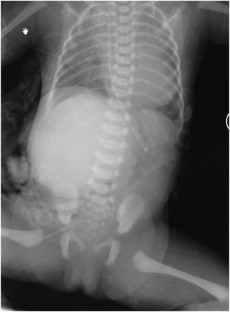

Herman, T., Siegel, M. Giant omphalocele, intrinsic duodenal obstruction. J Perinatol 31, 293–295 (2011). https://doi.org/10.1038/jp.2010.163